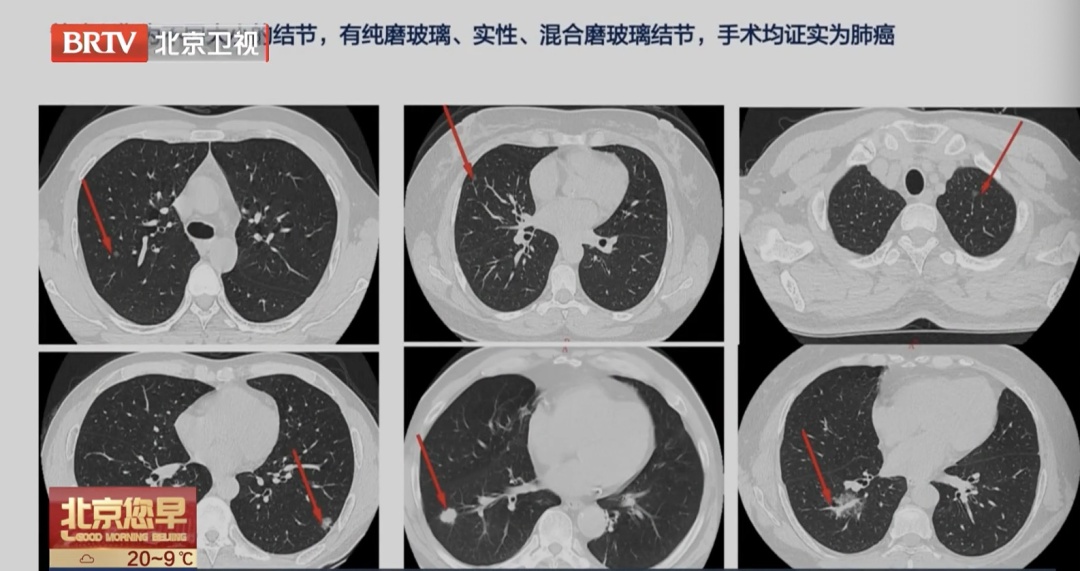

随着CT分辨率提高,双肺多发磨玻璃结节的检出越来越常见。很多人一看到“多发”两个字就慌了,担心是不是癌症扩散了。

北京胸科医院医学影像科主任、主任医师侯代伦介绍:“现在CT分辨率越来越高,一些较小的,比如1到2毫米的结节也得以显示,所以有肺结节的人越来越多,我们不必恐慌,多个肺结节的处理是有科学策略的。”

双肺多发磨玻璃结节,大多数情况下是多原发早期肺癌或癌前病变,而不是晚期肺癌的肺内转移。两者的治疗策略完全不同。

侯代伦介绍:“我们不能一次性切除双肺多结节,首先要进行多学科的会诊,进行个性化的分析,然后精准地打击一个,后续再随访多个。”